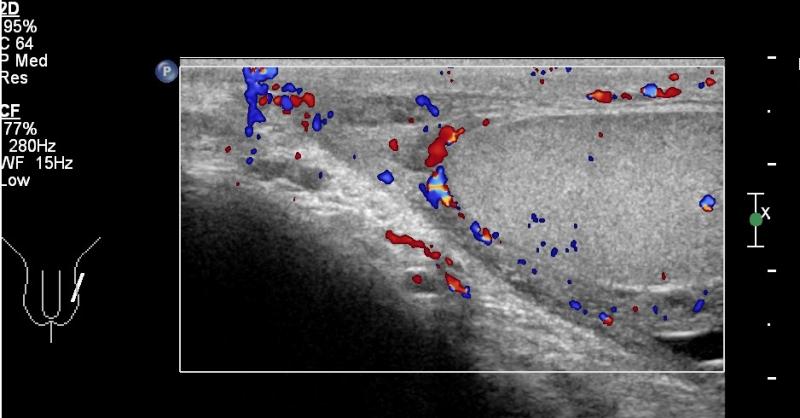

Przypadek 8: 16-latek z bólem moszny po stronie lewej od dnia poprzedniego. W badaniu przedmiotowym zaczerwienienie i niewielki obrzęk moszny po stronie lewej.

Rozpoznanie: W badaniu usg widoczne pogrubienie i przekrwienie najądrza lewego i osłonek jądra lewego. Nieco zwiększona ilość płynu w mosznie, płyn z licznymi przegrodami. Cechy stanu zapalnego najądrza lewego. Struktura obu jąder w normie.